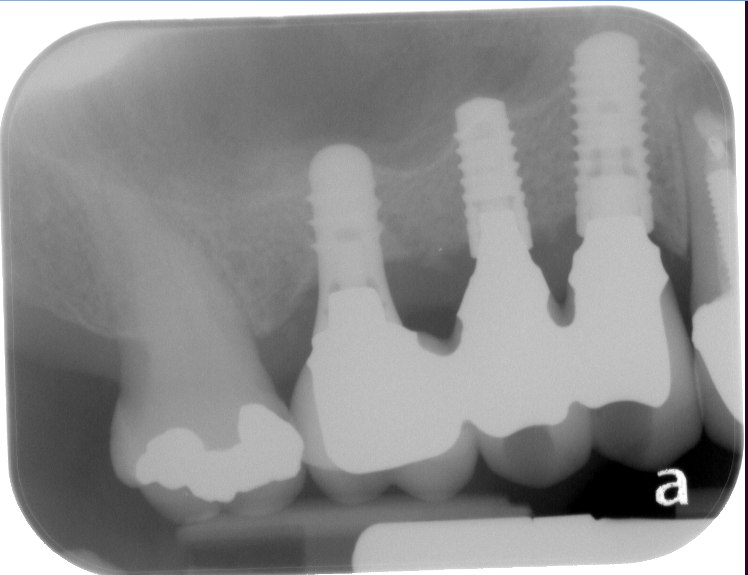

Sinus Lift Implant Vancouver Burnaby Periodontist Implant Dentist IMPreESS Perio

Dental Implant Centre in Vancouver Burnaby Sinus Lift Dental implant Surgery Dr. Noroozi Implant Specialist IMPrESS Perio Implant Center.001

Sinus Lift, Bone Graft, Implants Dr. Noroozi IMPrESS Perio Implant Center